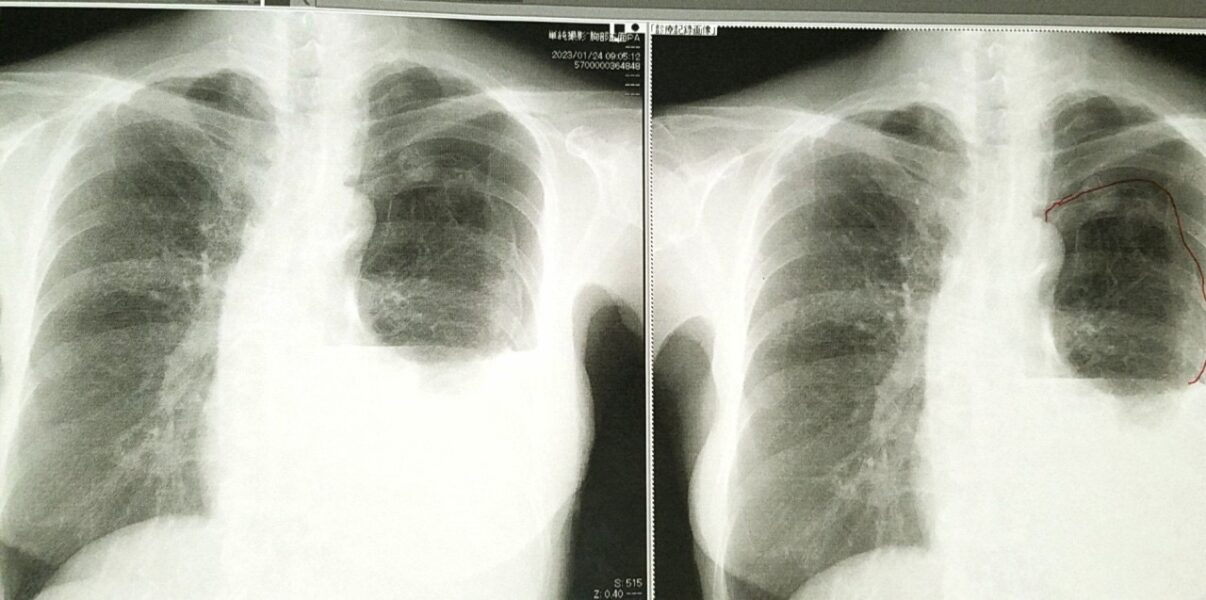

写真は24日(火曜日)朝のレントゲンです。術直後の経験した事のない違和感は、胸腔内の大量出血の為だった様です。2度のCTの後、夕方、呼吸器外科で肋骨の間からドレーン(管)を入れて貰ったところ、今朝までの排血量は1200cc。30日(月曜日)まで空気漏れが改善しなければ、手術と輸血も必要との事です。思い起こせば2011年の膵臓がん、卵巣がん以来、たくさんの摩訶不思議を頂いて来ました。 だから……